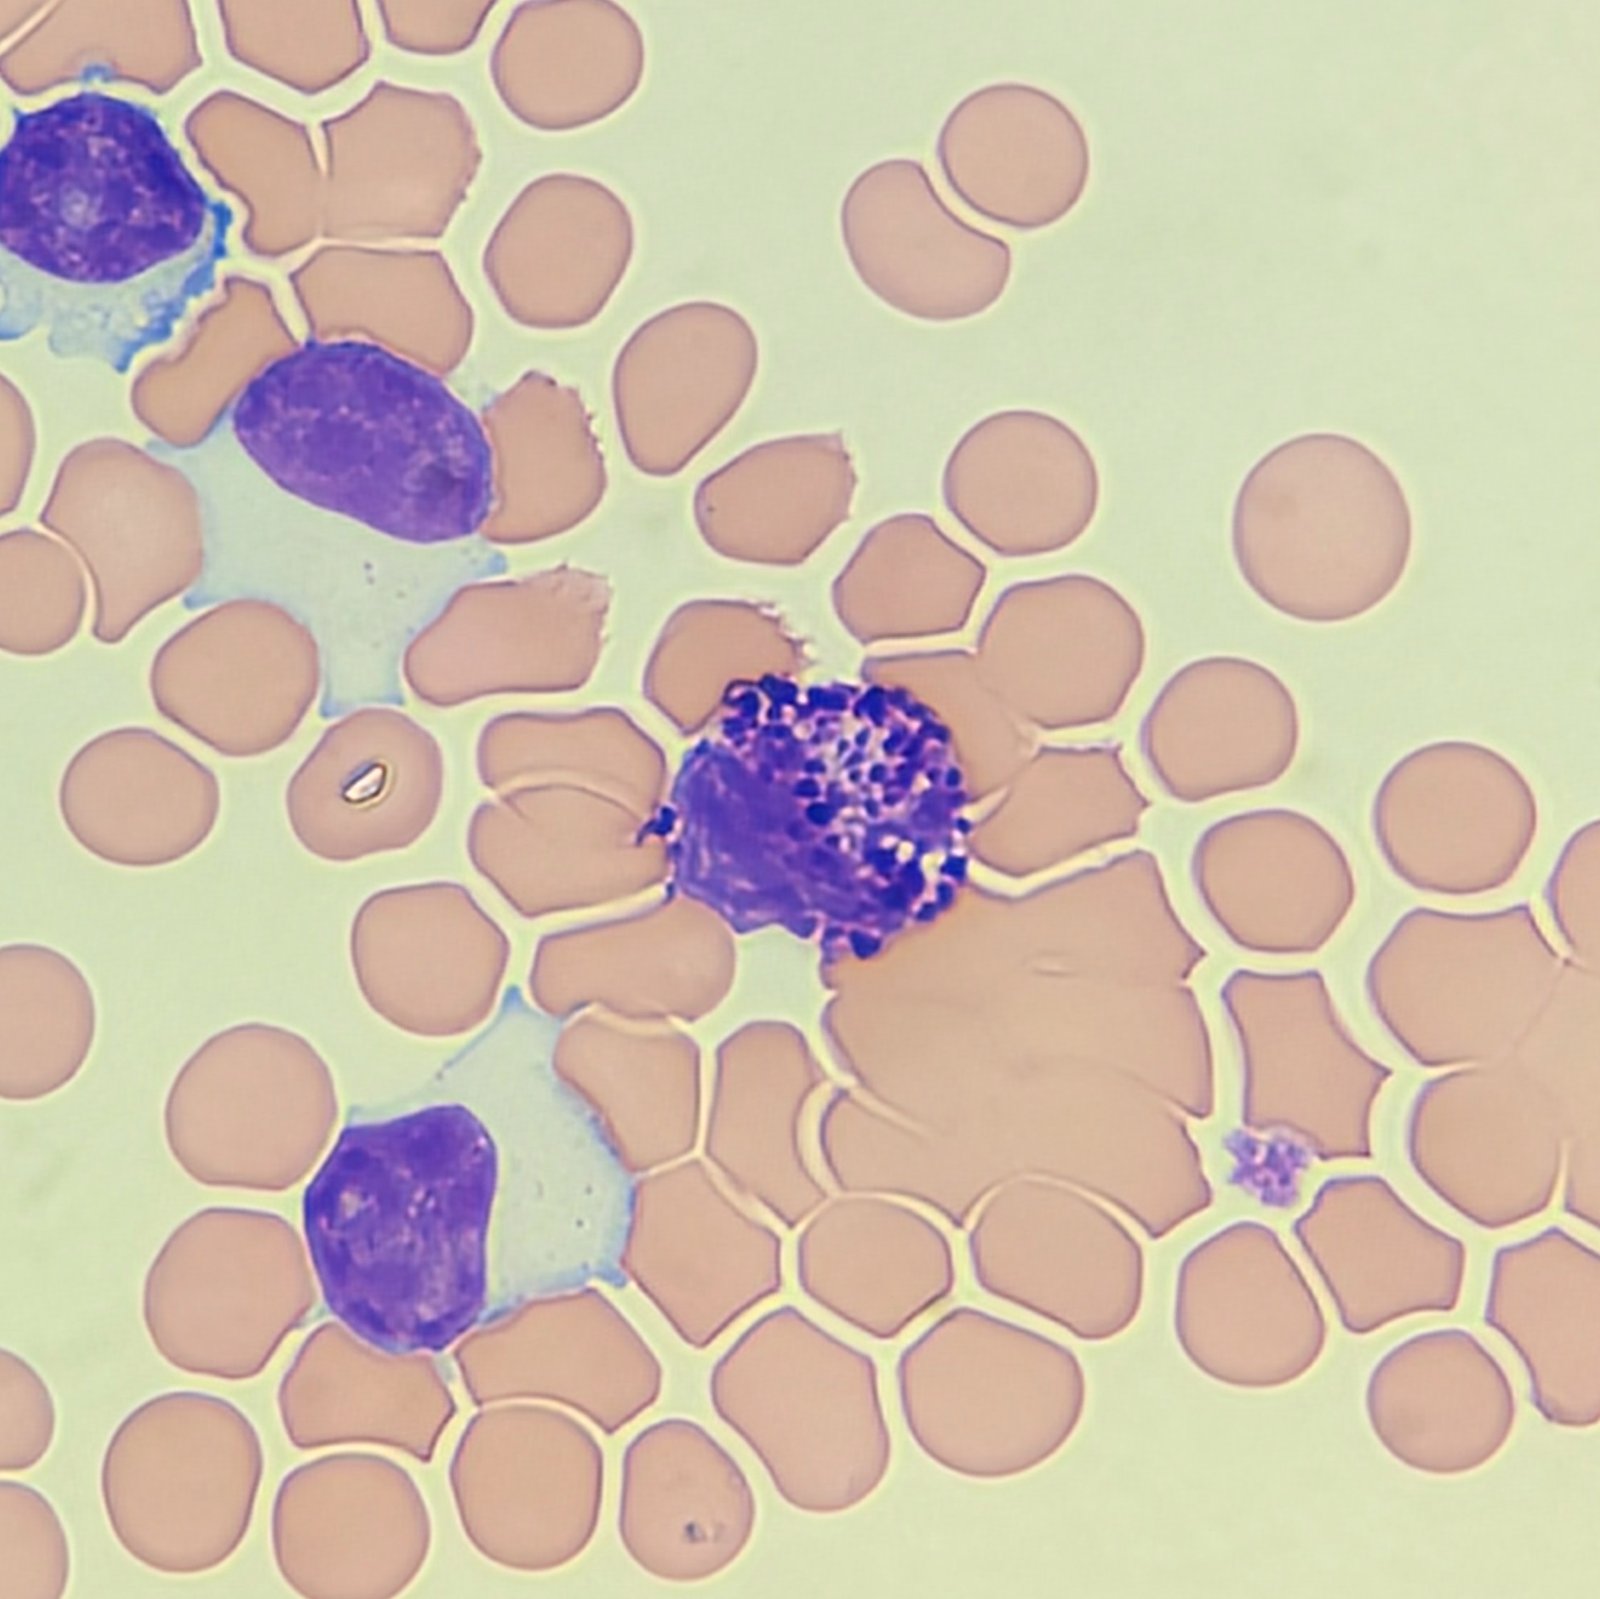

Cells may be seen in clumps, but “windows” between cells still allows for individual counting.

Macrophages are about the same size as mesothelial cells, so the two can often be confused. Macrophages can usually be differentiated by the presence of vacuoles and a lacey chromatin. If both cell types are present and differentiation is difficult, take a look around the slide to get an idea of each kind of morphology before starting a differential.

Both malignant cells and mesothelial cells can clump together. However, malignant cells will not have the windows between cells.